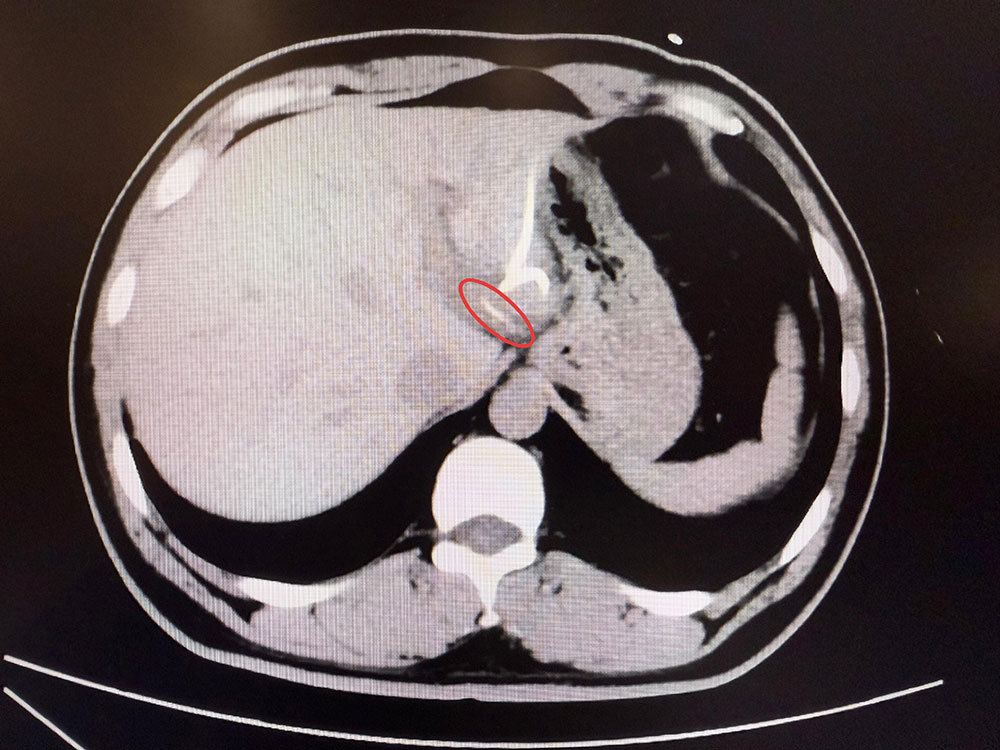

直到CT检查时,医生才惊讶地发现,李先生肝脏左叶靠近胃贲门处有一条细长的高密度影,形似鱼刺。原来,那根鱼刺在吞咽后穿透了胃壁,从贲门区域钻入肝脏,引发感染与脓肿。在简单进行肝脓肿介入穿刺引流后,当地外科医生评估后认为,要彻底清除异物,需要进行左半肝切除手术,但这对于李先生来说,创伤大、风险高,他难以接受。

患者李先生影像检查。本文图片均来自复旦大学附属中山医院